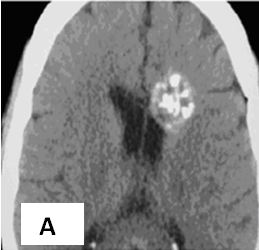

Hình 1. Hình ảnh di căn não đa ổ trước tiêm thuốc (A) và sau tiêm thuốc (B) của bệnh nhân ung thư phổi không phải tế bào nhỏ.

Trước tiêm thuốc: Tổn thương thường là khối đồng hay giảm tỉ trọng. Đôi khi có tỉ trọng cao hơn vùng nhu não liền kề như trong trường hợp chảy máu trong u di căn hoặc lắng đọng canxi.

Sau tiêm thuốc: Tổn thương ngấm thuốc dạng lốm đốm, dạng nốt hay hình vòng.